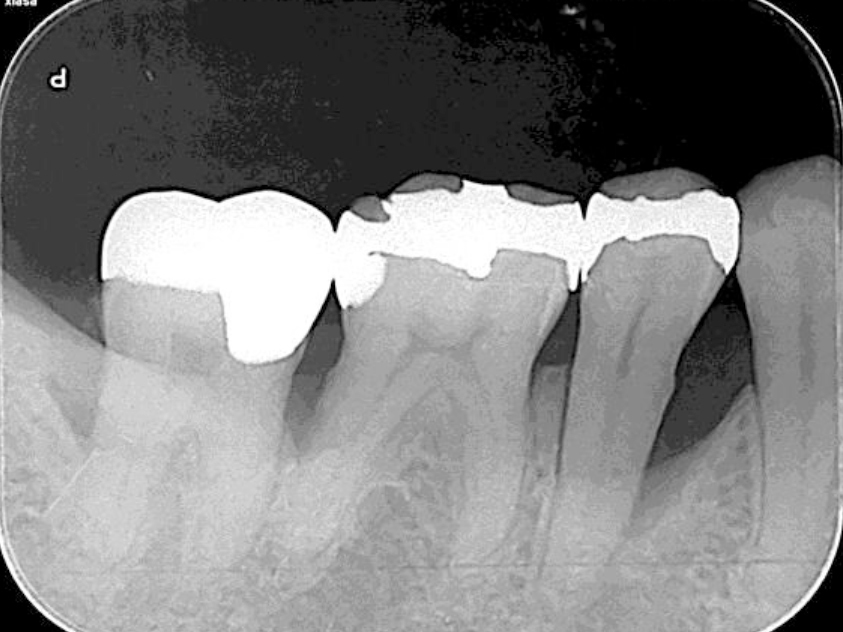

処置前(レントゲン)

浜松市中区の症例紹介 歯周外科

根管治療・歯周基本治療(レントゲン)

歯周基本治療後

(レントゲン)

初診時年齢:

治療:歯周病治療、う蝕治療

治療法:歯周基本治療、感染根管治療

治療期間:6ヶ月

費用:保険診療

リスク・副作用:感染根管処置中に腫れ、痛みが出ることがありますが時間とともに治ります。